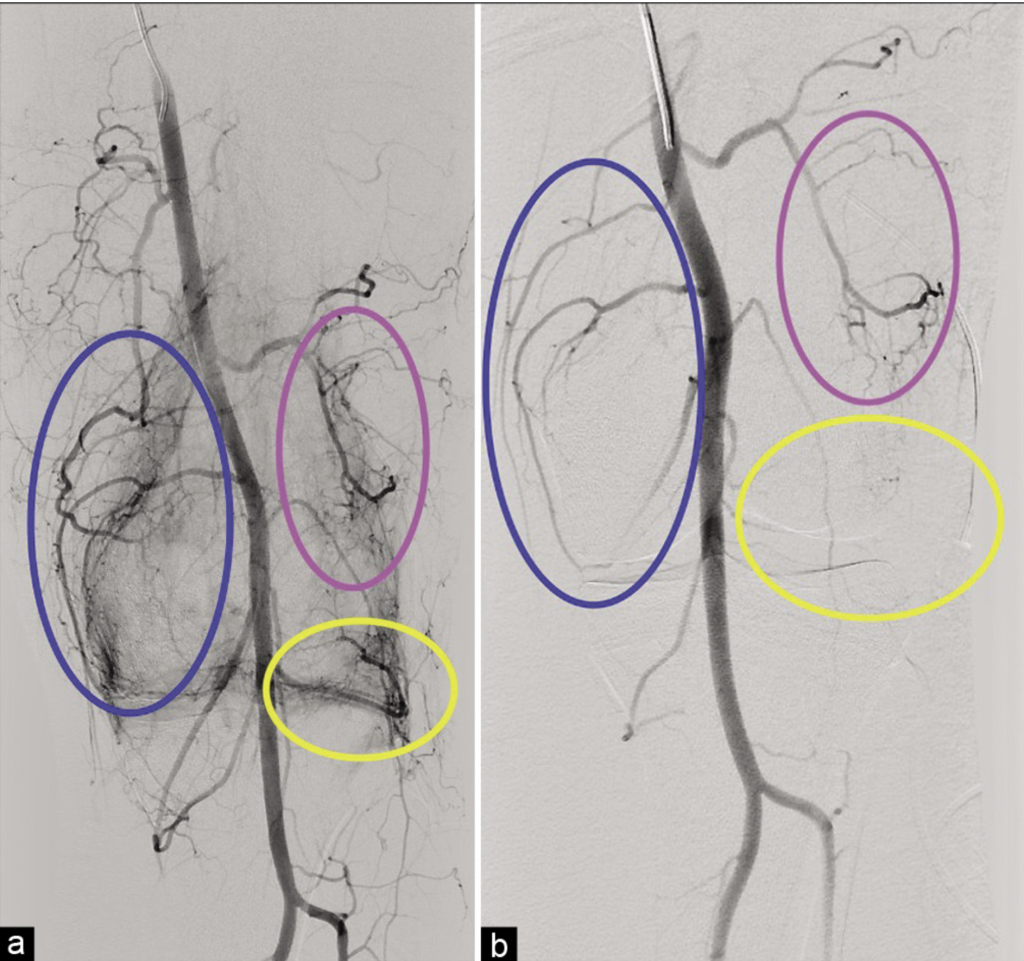

Attēlā: a. Hipervaskulārie apvidi ap ceļa locītavu atbilst aktieviem iekaisuma procesiem un ir sāpju avots. b. Uzreiz pēc embolizācijas redzama iekaisuma apvidu devaskularizācija.

Stradiņa slimnīcā ieviesta moderna un efektīva ārstēšanas metode, kas būtiski mazina sāpes un uzlabo dzīves kvalitāti pacientiem ar osteoartrītu, sinovītu un fascītu. Locītavu embolizācija ir minimāli invazīva ārstēšanas metode, kas piemērojama dažādām locītavām, tostarp ceļa, pleca, elkoņa, gūžas, plaukstas un pēdas locītavām. Lielākajā daļā gadījumu sāpju mazināšanās novērojama jau uzreiz pēc procedūras, un efekts var saglabāties no sešiem līdz pat 24 mēnešiem. Procedūra tiek veikta lokālā anestēzijā.